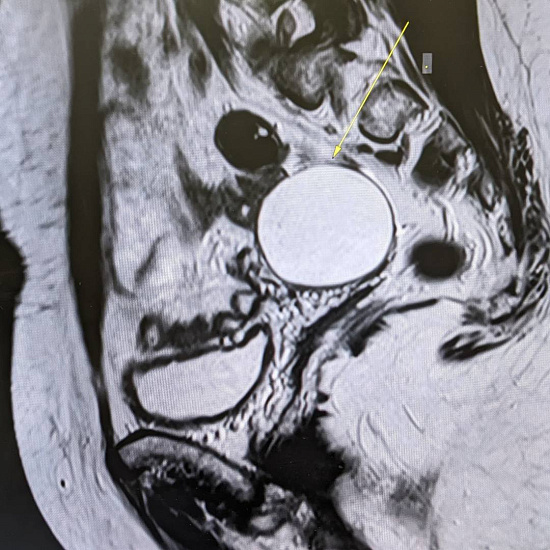

53-летняя пациентка обратилась к гинекологу в рамках программы check-up. При осмотре документации выяснилось, что на проведенных УЗИ-исследованиях от 2021 и 2023 года определяется образование правого яичника, требующее дифференциальной диагностики между эндометриоидной кистой и кистозно измененным яичником.

С целью оценки образования, уточнения его структуры и динамики роста пациентке было проведено МРТ органов малого таза.

При МРТ было выявлено жидкостное кистозное образование правого яичника без папиллярных разрастаний, гораздо больших размеров относительно первоначального УЗИ-исследования.

Учитывая анамнез пациентки, особенности структуры и размеры образования, была заподозрена цистаденома.